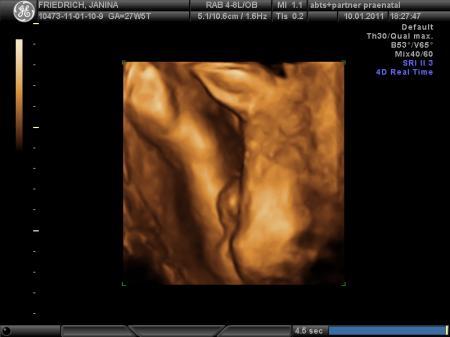

sooo...wie erwartet hat sich melvin nicht so gezeigt... wie wir es gerne hätten. schade, aber man konnte nix machen. Der Arzt hat so an meinem Bauch geruckelt und ich bin selbst nochmal aufgestanden um noch etwas zu hüpfen.... leider hatte er immer wieder seine hände im gesicht oder es war zwischen plazenta und kind kein fruchtwasser. :( Trotzdem hänge ich mal 2 Bilder ran... auf dem einen bild ist echt nicht zu verkennen, dass es ein junge wird... hihii.. ansonsten ist melvin ca. 40 cm und wiegt stolze 1200 gramm...

Süß, der kleine Melvin!! Und das 2. Bild ist echt cool!